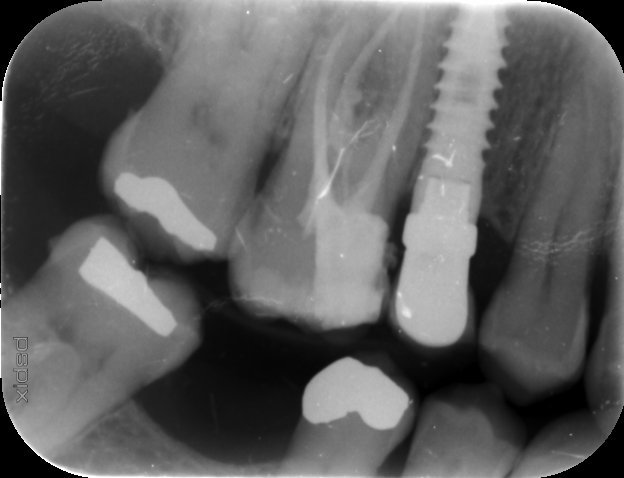

Hola a todos! Hace unos días acudió a consulta una paciente con una CSI que hay que cambiar por fractura de cerámica. Es de una clínica privada que ha cerrado [...]

Quiero repetir la prótesis, por lo que necesito saber qué implantes son. Gracias